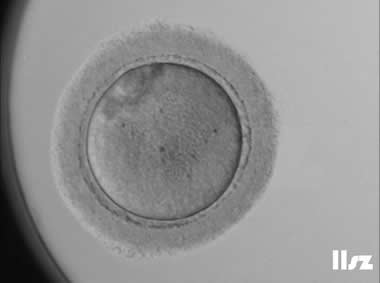

下面视频是胚胎在时差培养箱中培养至D3的整个过程,图片是D3(第68小时)的卵裂期胚胎图,本文D3胚胎评价是以D3时间点图片的形态学为依据,胚胎评级如下:

| Ⅰ级:该枚D3胚胎为8细胞,碎片不超过10%,因此评级为I级。 | |